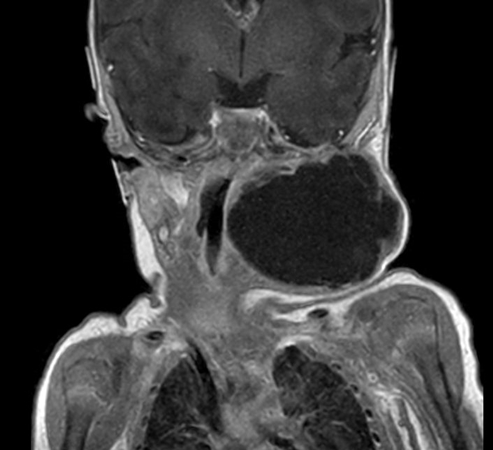

Coronal mDIXON XD - T1w TSE (Water only)

Coronal mDIXON XD - T1w TSE (In Phase)